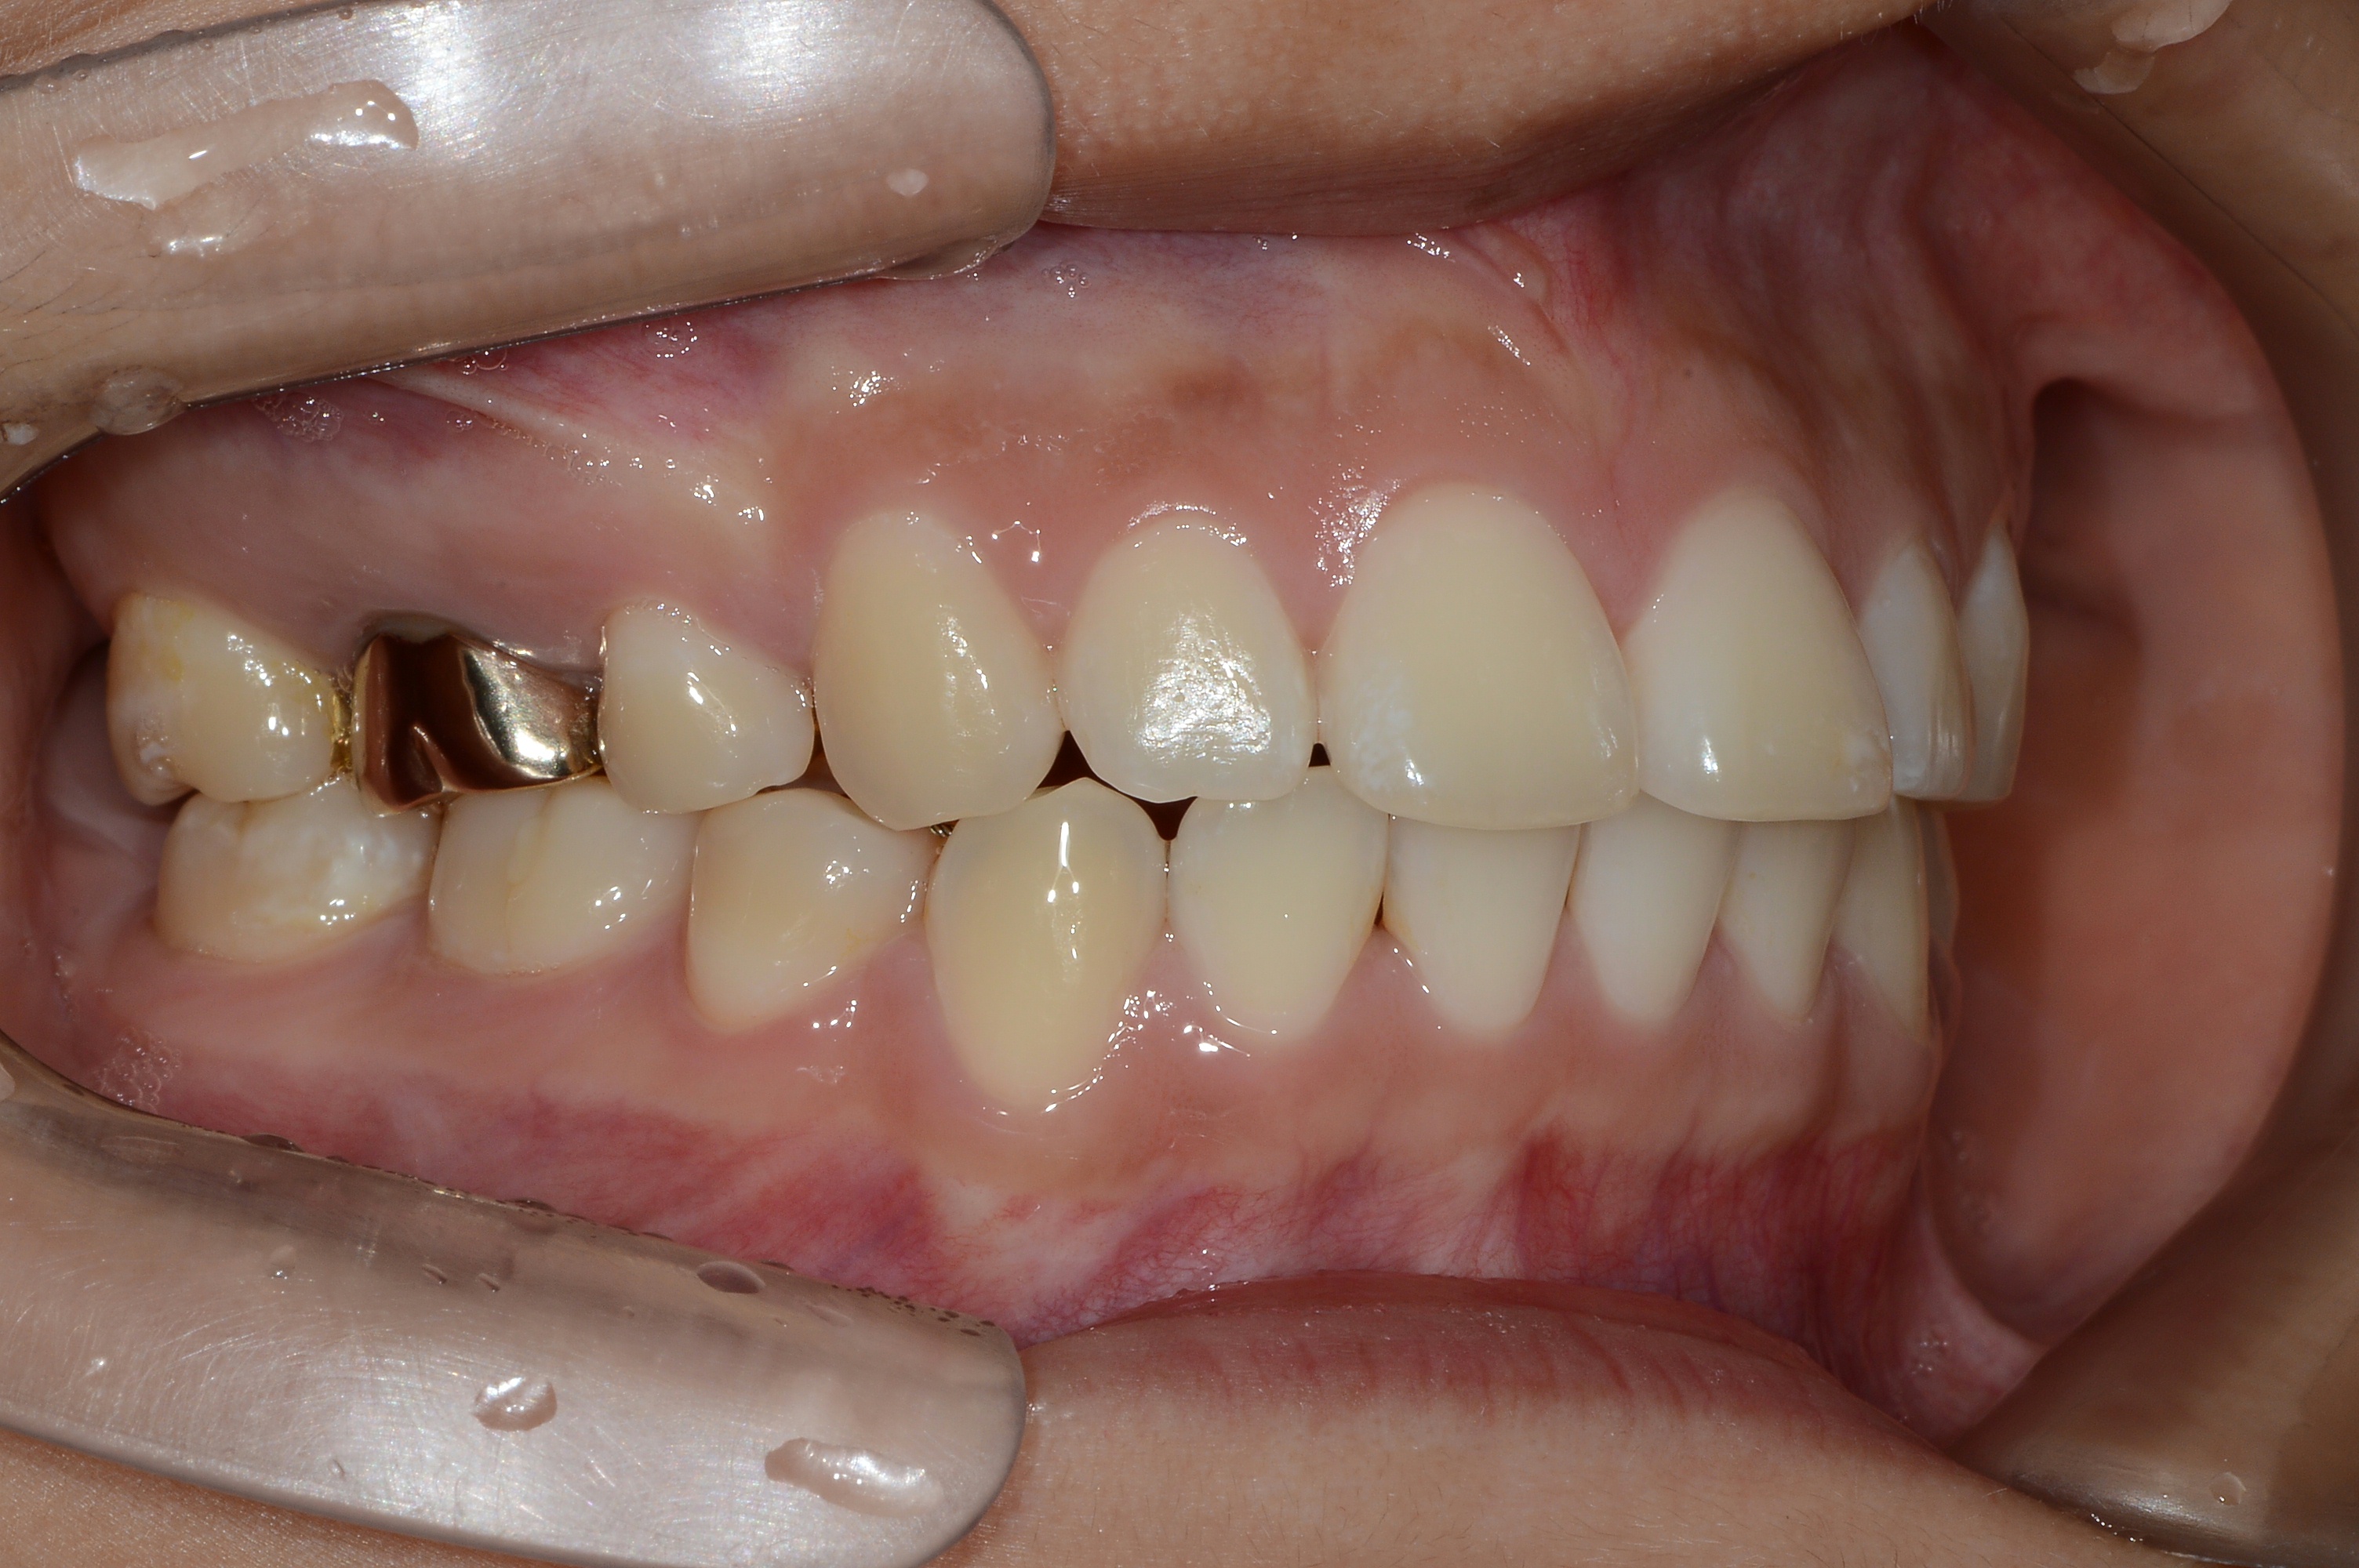

치료 후 사진입니다.